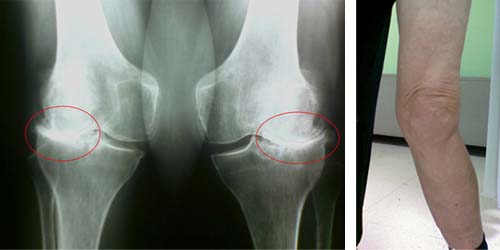

Артрозом коленного сустава (остеоартрозом, гоноартрозом, деформирующим артрозом) медики именуют дегенеративного характера заболевание коленного сустава, особенностью которого выступает разрушение хряща на суставных поверхностях.

Заболевание имеет следствием деформацию сустава в целом и нарушение его нормальных функций. В итоге развитие патологических процессов приводит к полному исчезновению хряща, а следовательно – к обнажению подлежащей под ним кости. Наиболее часто это заболевание наблюдается у пациентов, старше 50-ти лет. Большинство из них – женщины.